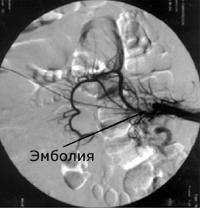

- КТ брюшной полости. Контрастирование пищеварительного канала с одновременной ангиографией абдоминальной части аорты назначается для верификации диагноза в сомнительных случаях. Исследование проводится для оценки стадии патологического процесса, измерения дуоденального просвета, величины угла, который образуют аорта и верхняя брыжеечная артерия.

• КТ брюшной полости. Контраст пищеварительного канала с одновременной ангиографией брюшной части аорты назначают для проверки диагноза в сомнительных случаях. Исследование проводится для оценки стадии патологического процесса, измерения просвета двенадцатиперстной кишки, величины угла, по которому аорта и форма верхней брыжеечной артерии.

КТ брюшной полости. Артериомезентериальная компрессия.